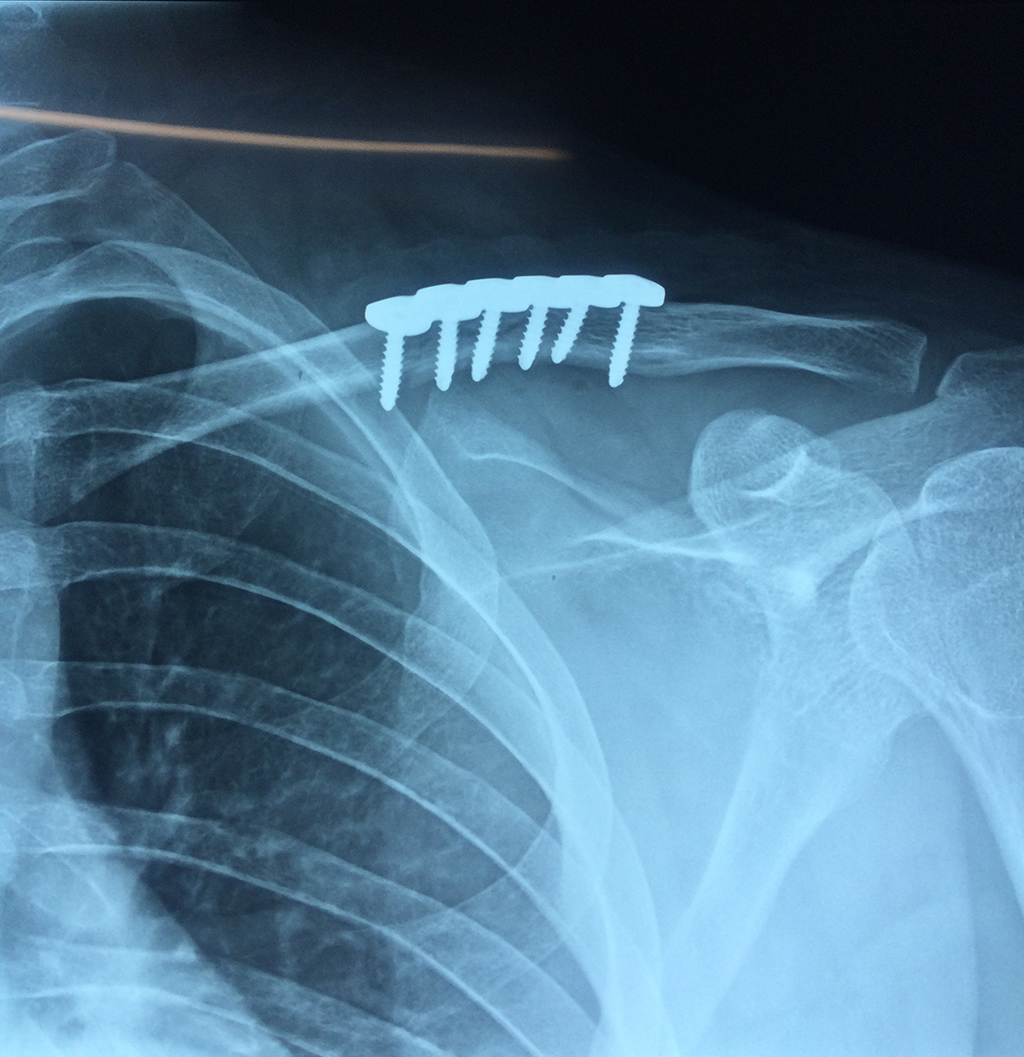

Cirugías de Húmero - Clavícula